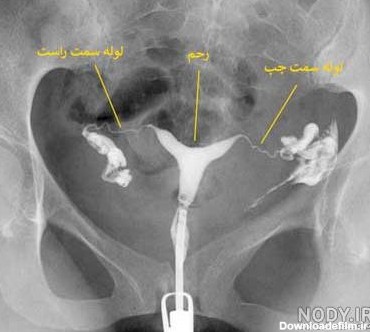

کیا عکس رنگی از رحم انداختن؟درد داره و تبادل نظر نی نی سایت دکتر گفت اگر اینبار حامله نشدی باید عکس رنگی از رحم بندازی ولی بچه های اینجا گفتن با بیهوشی گرفتن بدون...

بدو بدو میخوام در مورد عکس رنگی توضیح بدم و تبادل نظر نی ن سلام دوست جونا من دیروز رفتم واسه عکس رنگی از بس تو نی نی سایت بد شنیدم از ترس داشتم...